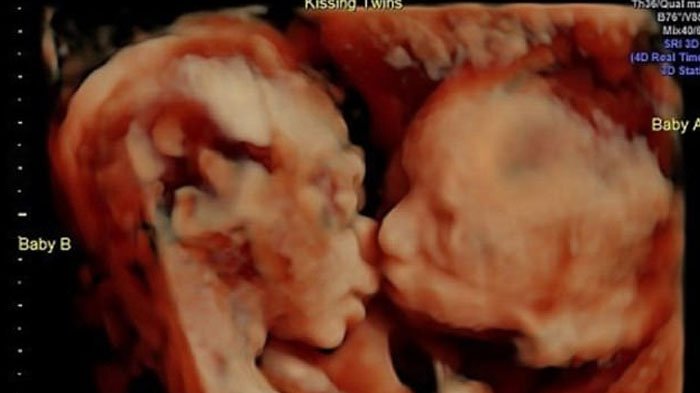

Bayi kembar berciuman dalam kandungan ibunya. Carissa Gill

Gill dan Randy melihat anak kembar perempuan mereka meringkuk dekat satu sama lain, kemudian si kembar itu saling ciuman di dalam rahim.

Gill dan Randy telah menamakan bayi kembar identik mereka, Isabella dan Callie.

"Isabella memberikan kasih sayang kepada Callie berupa ciuman di pipi," tulis Carissa dalam caption dari salah satu foto USG di Instagram.